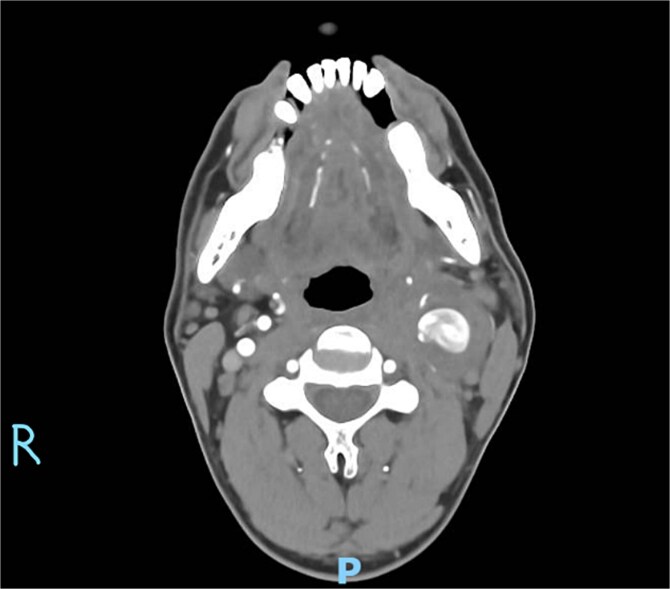

Figure 2.

Axial CT angiography demonstrating the left common carotid artery aneurysm.

On physical examination, vital signs were stable. A tender, pulsatile mass was palpable in the left anterior triangle of the neck (Fig. 1). Ultrasound revealed a 21 × 16 mm aneurysm of the left common carotid artery (CCA) with prominent reactive cervical lymphadenopathy. This was further evaluated with CT angiography, which confirmed a left CCA aneurysm involving the carotid bulb (Fig. 2).